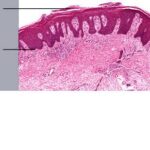

Psoriasis Vulgaris Histopathology The histologic picture of psoriasis vulgaris varies considerably with the stage of the lesion and usually is diagnostic only in early, scaling papules and near the margin of advancing plaques. |

The earliest pinhead-sized macules or smooth-surfaced papules show subtle histologic changes with a preponderance of dermal changes . At first, there is capillary dilation and edema in the papillary dermis, with a lymphocytic infiltrate surrounding the capillaries. The lymphocytes extend to the lower portion of the epidermis, where slight spongiosis develops. Then focal changes occur in the upper portion of the epidermis, where granular cells become vacuolated and disappear, and mounds of parakeratosis are formed. Neutrophils are usually seen only at the summits of some of the mounds of parakeratosis and appear scattered through an otherwise orthokeratotic cornified layer . These mounds of parakeratosis with neutrophils represent the earliest manifestation of Munro microabscesses . At this stage, which is characterized clinically by an early scaling papule, a histologic diagnosis of psoriasis can often be made. In some cases, when there is marked |

exocytosis of neutrophils, they may aggregate in the uppermost portion of the spinous layer to form small spongiform pustules of Kogoj. Lymphocytes remain confined to the lower epidermis, which, as more and more mitoses occur, becomes increasingly hyperplastic. The epidermal changes are at first focal, but later become confluent, leading clinically to plaques. In the fully developed lesions of psoriasis, as best seen at the margin of enlarging plaques, the histologic picture is characterized by (a) acanthosis with regular elongation of the rete ridges with thickening in their lower portion; (b) thinning of the suprapapillary epidermis with the occasional presence of small spongiform pustules; (c) pallor of the upper layers of the epidermis; (d) diminished to absent granular layer; (e) confluent parakeratosis; (f) the presence of Munro microabscesses; (g) elongation and edema of the dermal papillae; and (h) dilated and tortuous capillaries . |

The rete ridges show considerable elongation and extend downward to a uniform level, resulting in regular acanthosis . They are often slender in their upper portion but |

show thickening ("clubbing") in their lower portion. Not infrequently, adjacent rete ridges seem to coalesce at their bases due to tangential sectioning. Usually, intercellular and intracellular edema is absent in the rete ridges, and keratinocytes located well above the basal layer show deep basophilia. In addition, mitoses are not limited to the basal layer as in normal skin but are also seen above the basal layer. This, together with a considerable lengthening of the basal cell layer due to elongation of the rete ridges, results in a marked increase in the number of mitoses. This increase has been calculated to be 27 times the number of mitoses in uninvolved skin . |

The suprapapillary epidermis appears relatively thin in comparison with the markedly elongated rete ridges, and the cells in the upper layers of the epidermis may appear enlarged and pale stained as a result of intracellular edema and hypogranulosis. Keratinocytes beneath the parakeratotic cornified layer may be intermingled with neutrophils . The histologic picture is then that of a small spongiform pustule of Kogoj . Although it is only a micropustule, it is nevertheless of the same type as the much larger macropustules seen in pustular psoriasis. Such a spongiform pustule, highly diagnostic for psoriasis and its variants, shows aggregates of neutrophils within the interstices of a spongelike network formed by degenerated and thinned epidermal cells |

Munro microabscesses are located within the parakeratotic areas of the cornified layer . They consist of accumulations of neutrophils and pyknotic nuclei of neutrophils that have migrated there from capillaries in the papillae through the suprapapillary epidermis. As a rule, Munro microabscesses are easily found in early lesions but are few in number or absent in longstanding lesions . The dermal papillae, in accordance with the elongation and basal thickening of the rete ridges, are elongated and club shaped. They show edema, and the capillaries within them appear dilated and tortuous. A relatively mild inflammatory infiltrate is present in the upper dermis and the papillae. It consists of lymphocytes, except in early lesions, in which neutrophils are also present in the upper portion of the papillae . |